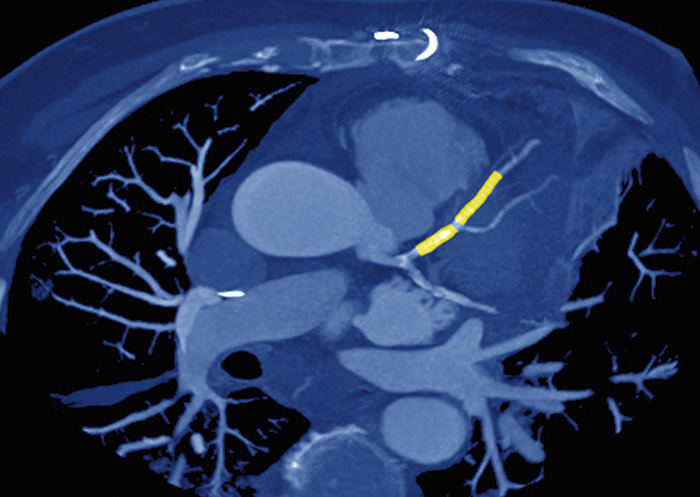

Perkutan koronarintervention är ett exempel på den interventionella radiologins betydelse i den kliniska vardagen. Foto: Sovereign/ISM/SPL/IBL

Denna utveckling fick sådan genomslagskraft att det i grunden har förändrat andra specialiteter som kardiologi, kärlkirurgi och toraxkirurgi. Utveckling av kranskärlsröntgen till den i dag omfattande verksamheten av perkutana koronarinterventioner har ersatt mycket av kranskärlskirurgin. Också den öppna kärlkirurgin har till stor

del ersatts av endovaskulära metoder, och utveckling av neurointervention gör att mycket av den intrakraniella aneurysmkirurgin nu kan göras minimalinvasivt.